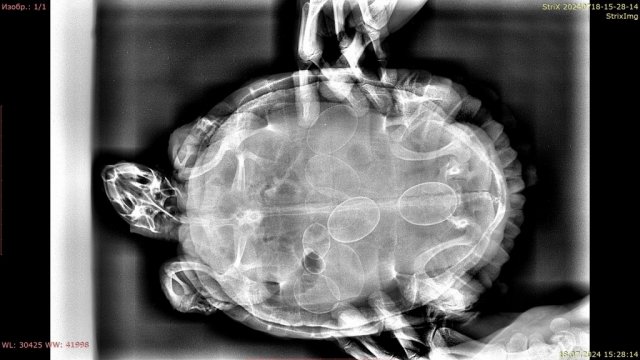

Консультанты moth Ваше имя: Мария Локация: Москва Опубликовано: 16 августа 2019 Консультанты Опубликовано: 16 августа 2019 (изменено) @Инна Г Если она крутится, плавает и держит голову преимущественно в одну сторону, то это поражение мозга на противоположной стороне. Скорее всего, геморрагический инсульт, вызванный травмой. Но это никак не проверить из-за её размера. Если это так, то оно либо само пройдёт либо останется вот так, либо будет проявляться в виде эпилепсии и т.д. Вам нужно уровень воды оставить такой, чтобы она не могла утонуть в припадке, но могла перевернуться в воде, если вдруг упадёт на спину. крен может быть либо отдельным симптомом той же пневмонии или переедания, либо следствием травмы. Лечить такую маленькую черепаху должен врач. У Васильева, по-моему, в субботу должен быть приём в Клыке. если приём не скоро, то можно сделать укол Дексафорт 0.01мл в мышцу попы, он снимает отёк Изменено 16 августа 2019 пользователем moth

Инна Г Ваше имя: Инна Локация: Москва Опубликовано: 16 августа 2019 Автор Опубликовано: 16 августа 2019 (изменено) Да у нее вроде травмы и не было, она ниоткуда не падала точно... Вчера еще утром за рыбами охотилась, очень резво плавала., а к вечеру ее перекосило... Может, свернула себе что-то в погоне? но думаю, что это маловероятно. Она меня в пластиковом контейнере маленьком пыталась укусить при кормлении, я руку отдернула и она немного ударилась о бортик. Но удар был очень слабый для травмы и тем более для инсульта. Сейчас уже вроде не крутится, просто плавает с креном и головой на бок...но очень мало, все лежит и греется под лампой. Записались на прием в зоопарке к Е.Ю.Дягилец на воскресенье, Васильеву не дозвонилась Изменено 16 августа 2019 пользователем Инна Г